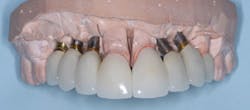

Observe Figs. 5-10 for a classic example of when crowns cannot be screwed onto abutments. The patient did not want to have bone grafting, and the implants were placed where there was minimally adequate bone. These implants were placed by a very competent periodontist. The significant angulation of the implants from the optimum angulation is easily observed with the impression copings on the implant bodies in Fig. 6. Custom abutments were mandatory, as shown in Fig. 6. The resultant crowns (Figs. 9-10) created a very acceptable esthetic result. It is very obvious that if crowns had been screwed onto the implants without an abutment, the screw entry would have been through the facial or incisal portion of the crowns.

FIG. 9 -- The crowns on the custom abutments.

FIG. 10 -- A happy patient. This patient could not have screws through the crowns because the angulation of the implant placement would have led to screw holes coming through the facial surfaces of the crowns.